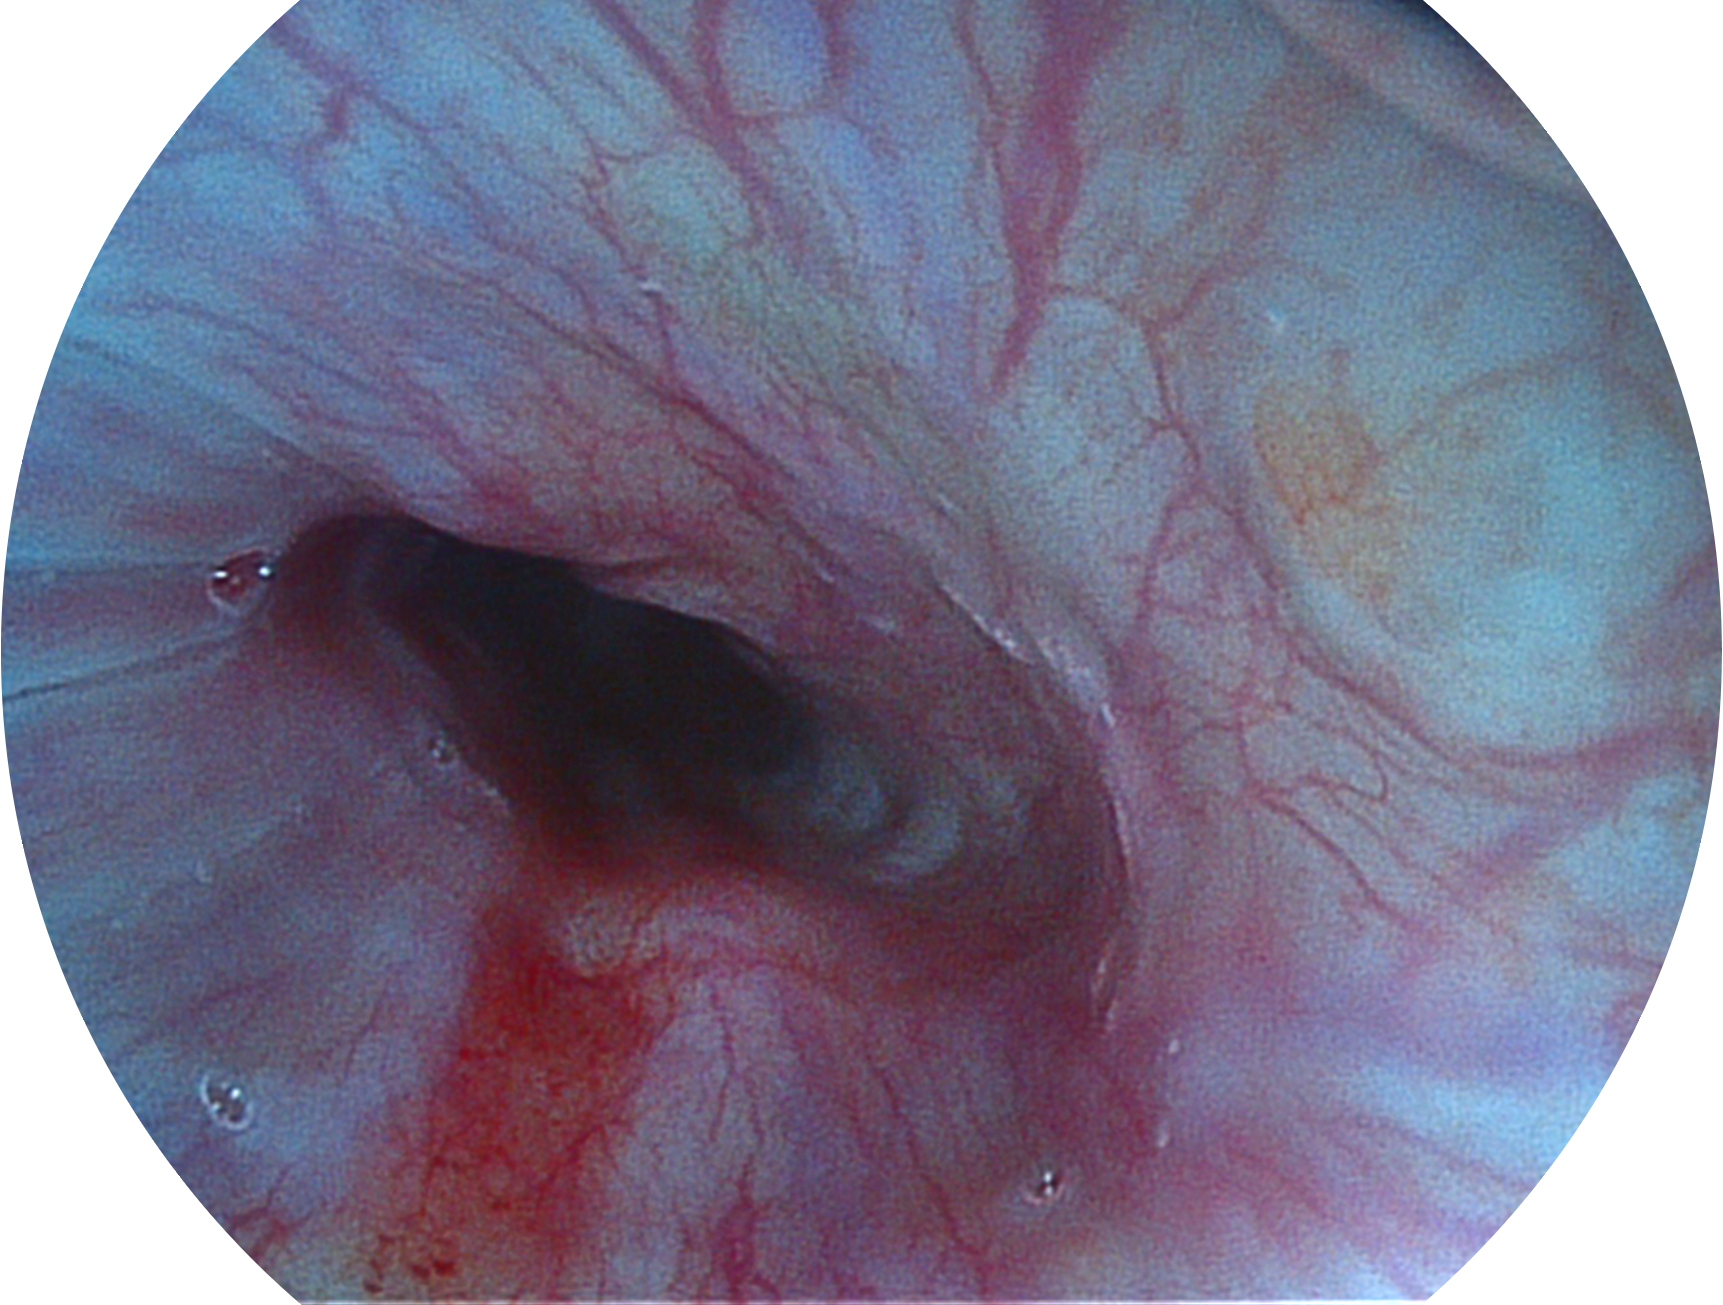

球速体育入口新开发的内镜染色技术,主要是基于多波长LED 光源的开发,VLS-55Q 四波长LED 光源是由四个不同颜色的LED光按照相应照明模式所规定的特定发光比例进行合束后形成,合束后形成的照明光的光谱由红光、绿光、蓝光及蓝紫光这四个不同的波段范围构成。具有更高光谱自由度,通过光谱比例的控制,实现了聚谱成像技术,英文全称为“Spectral Focused Imaging, SFI”,缩写为“SFI”和光电复合染色成像技术,英文全称为“Versatile Intelligent Staining Technology, VIST”,缩写为“VIST”。